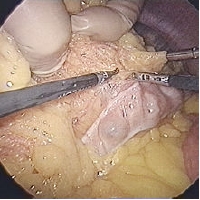

腹腔鏡で見た手術中のおなかのなかの様子。”大きな”手が見えます。今高熱が持続し入院、精査をしているときに、たまたま見つかった早期胃ガンの患者さんがいるので腹腔鏡補助下胃切除LADGできないかと内科の主治医から相談があった。詳しく話を聞くと不明熱は最終的に血球貪食症候群という希な疾患らしい。治療として副腎皮質ホルモン、いわゆるステロイドを内服しているとのことであった。この薬は魔法のような薬であり炎症を強く抑える働きがある一方、外科的立場からすると縫合不全がおこるリスクが上昇する、感染に弱くなる、副腎不全になる、胃潰瘍になりやすくなる、等の懸念がある。またガンの胃内での位 置が手術を行う場合、非常に重要である。場所によって手術方法がかなり異なるからである。胃カメラでみると胃のちょうど中央付近とのことであったが実際バリウムを飲んだレントゲンを撮ってみるとかなり病変は上であった・・・つまり胃を残すことができないと判断せざるを得なかった。つまり胃を全部とってしまう手術が必要ということだ。

手術は全身麻酔下に行われた。まずはじめに上腹部にものさしで計った8cmの線を引いて正確にそのサイズに開腹した。その小さな開腹創にLapDisc®(Hakko)を装着する。左手を腹腔内に挿入しそれをガイドに臍上から1cm の皮膚切開をおいて腹腔鏡を挿入する12mmのポートを挿入した。患者さんの右側腹部に術者の右手用5mmのポート、左側に助手用の5mmポートを2本、合計4個のポートを挿入した。LapDiscのアイリスを手首に密着させるくらいに絞り空気の漏れを防ぐ。腹腔内に炭酸ガスを送り手術のための空間を確保する。カメラで見る手は巨大だ 。オペレーターの左手と助手の鉗子とのコンビネーショ